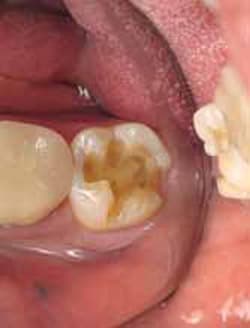

A 42-year-old male was scheduled to have two Class II posterior direct composite restorations on teeth Nos. 18 and 19 after radiographs revealed caries under old restorations (Figure 2). A 1556 carbide bur was used to remove the old restoration and caries, as well as to prepare the cavity. When composite is the restorative material to be used, a traditional G.V. Black geometrical preparation is not necessary, because composite does not require minimum depth, minimum width, or mechanical retention like amalgam does. The key is to fully remove the caries in the most tooth-conserving fashion.